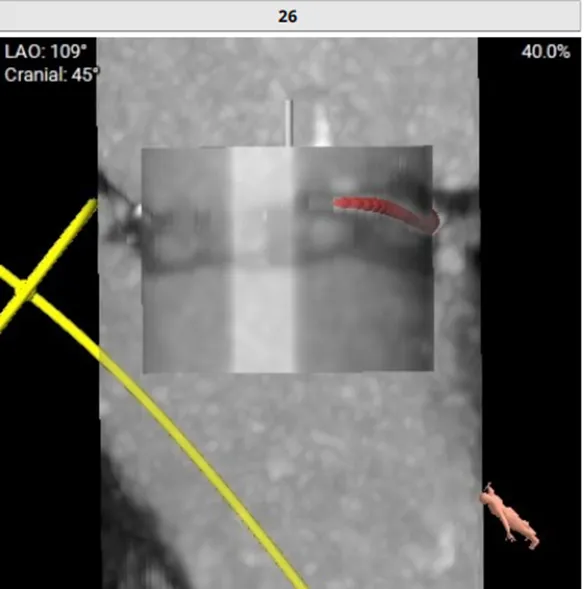

RAO:23° CRA:25°

Positioning heigh: 90/10 preferred